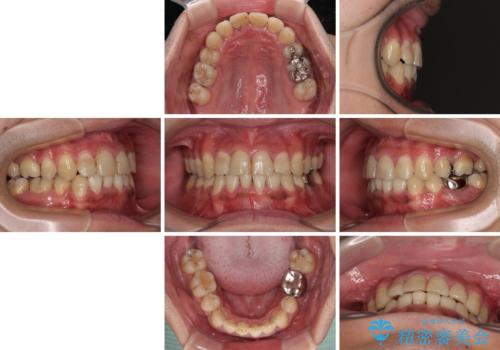

重なって磨きにくい上下の前歯 ワイヤー装置での抜歯矯正

- 前歯のデコボコを改善したいと来院された患者様です。

口元の突出感はないものの、上顎前歯のデコボコが著しかったため、上下顎左右小臼歯4本を抜歯することとしました。

第二小臼歯抜歯の矯正治療は、治療期間が長引くことが多いですが、動きが非常に良く、予定の治療期間で終えることができました。

上下の正中も思っていた以上に良い位置に改善されました。